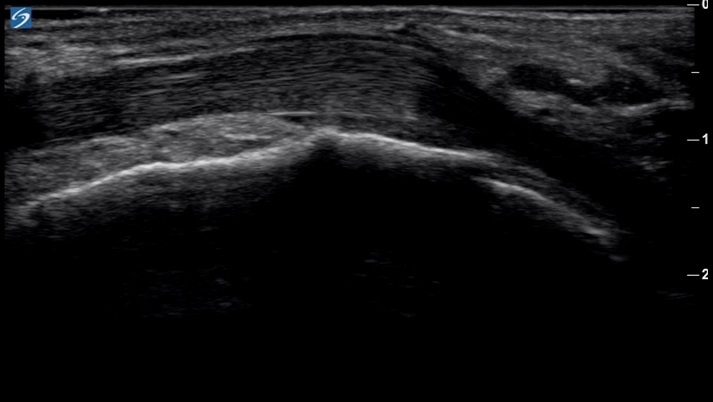

Bild: Fuß und Sprunggelenk, Peronealsehne, lange Achse